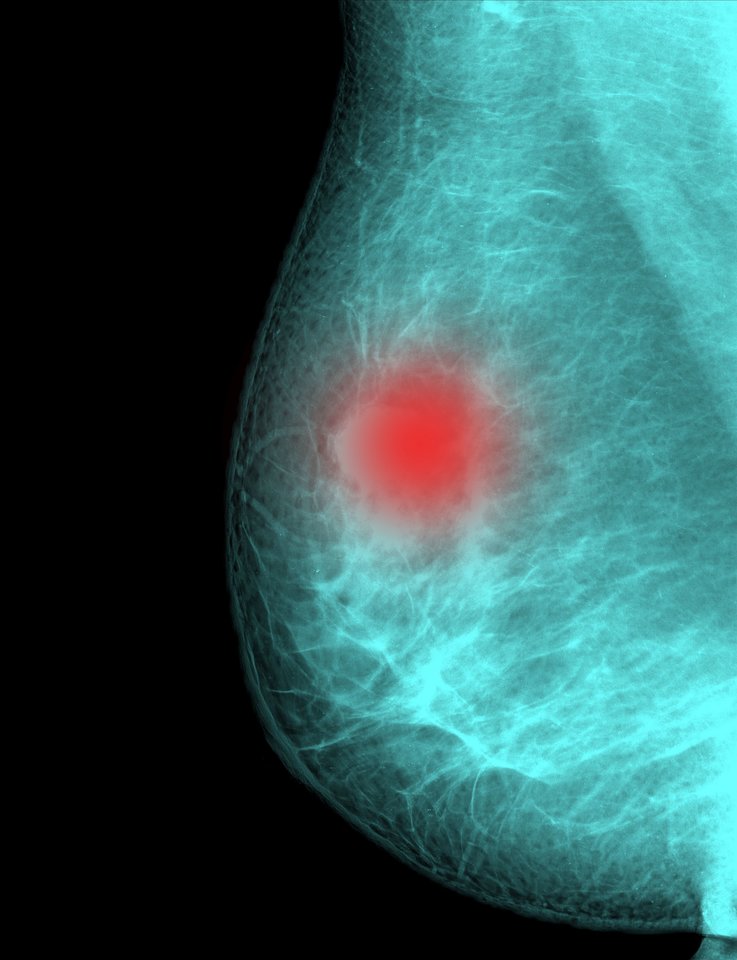

„Krūties vėžys išlieka dažniausia onkologine liga tarp premenopauzę ir menopauzę išgyvenančių moterų. Būtent todėl šios amžiaus grupės moterys – nuo 50 iki 69 metų, kviečiamos aktyviau dalyvauti prevencinėje mamografinės patikros programoje. O tai, kad krūties vėžiu suserga ir jaunesnės moterys, siejama su paveldimais mutavusiais BRCA1, BRCA2 genais.

Nustačius patogeninį BRCA1 ar BRCA2 geno variantą, pacientas priskiriamas padidintos rizikos grupei, jam sudaromas specialus sveikatos priežiūros planas, siekiant užkirsti kelią onkologinei ligai. Pacientui skiriami kryptingi ir detalūs tyrimai, leidžiantys anksti nustatyti ir pagydyti onkologinę ligą (mamografija, krūtų MRT, vyrams – prostatos antigeno tyrimai) arba rekomenduojamos profilaktinės krūtų, kiaušidžių šalinimo operacijos.